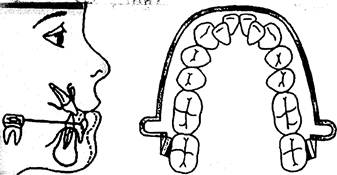

Аппаратом функционального действия является губной бампер. Он состоит из собственной вестибулярной дуги на нижний зубной ряд. В конце дуги изогнуты упоры с тем, чтобы они располагались перед трубками. Последние припаяны (приварены) к кольцам, фиксированным на первых нижних молярах. В переднем отделе дуга бампера отстоит от передних зубов на 2 мм и может быть выполнена в виде губного пелота. В боковых участках дуга бампера отстоит от зубного ряда на 4—5 мм.

При пользовании губным бампером происходит изменение миоди-намического равновесия между мышцами-антагонистами. Внешняя

мускулатура оттягивается от нижнего зубного ряда, обеспечивая тем самым повышенную функцию языка. В результате применения губного бампера наблюдается развитие нижней челюсти, устраняется сужение зубного ряда в сагиттальном и трансверсальном направлениях. С помощью губного бампера можно дистально перемещать моляры или стабилизировать их положение (рис. 13.52).